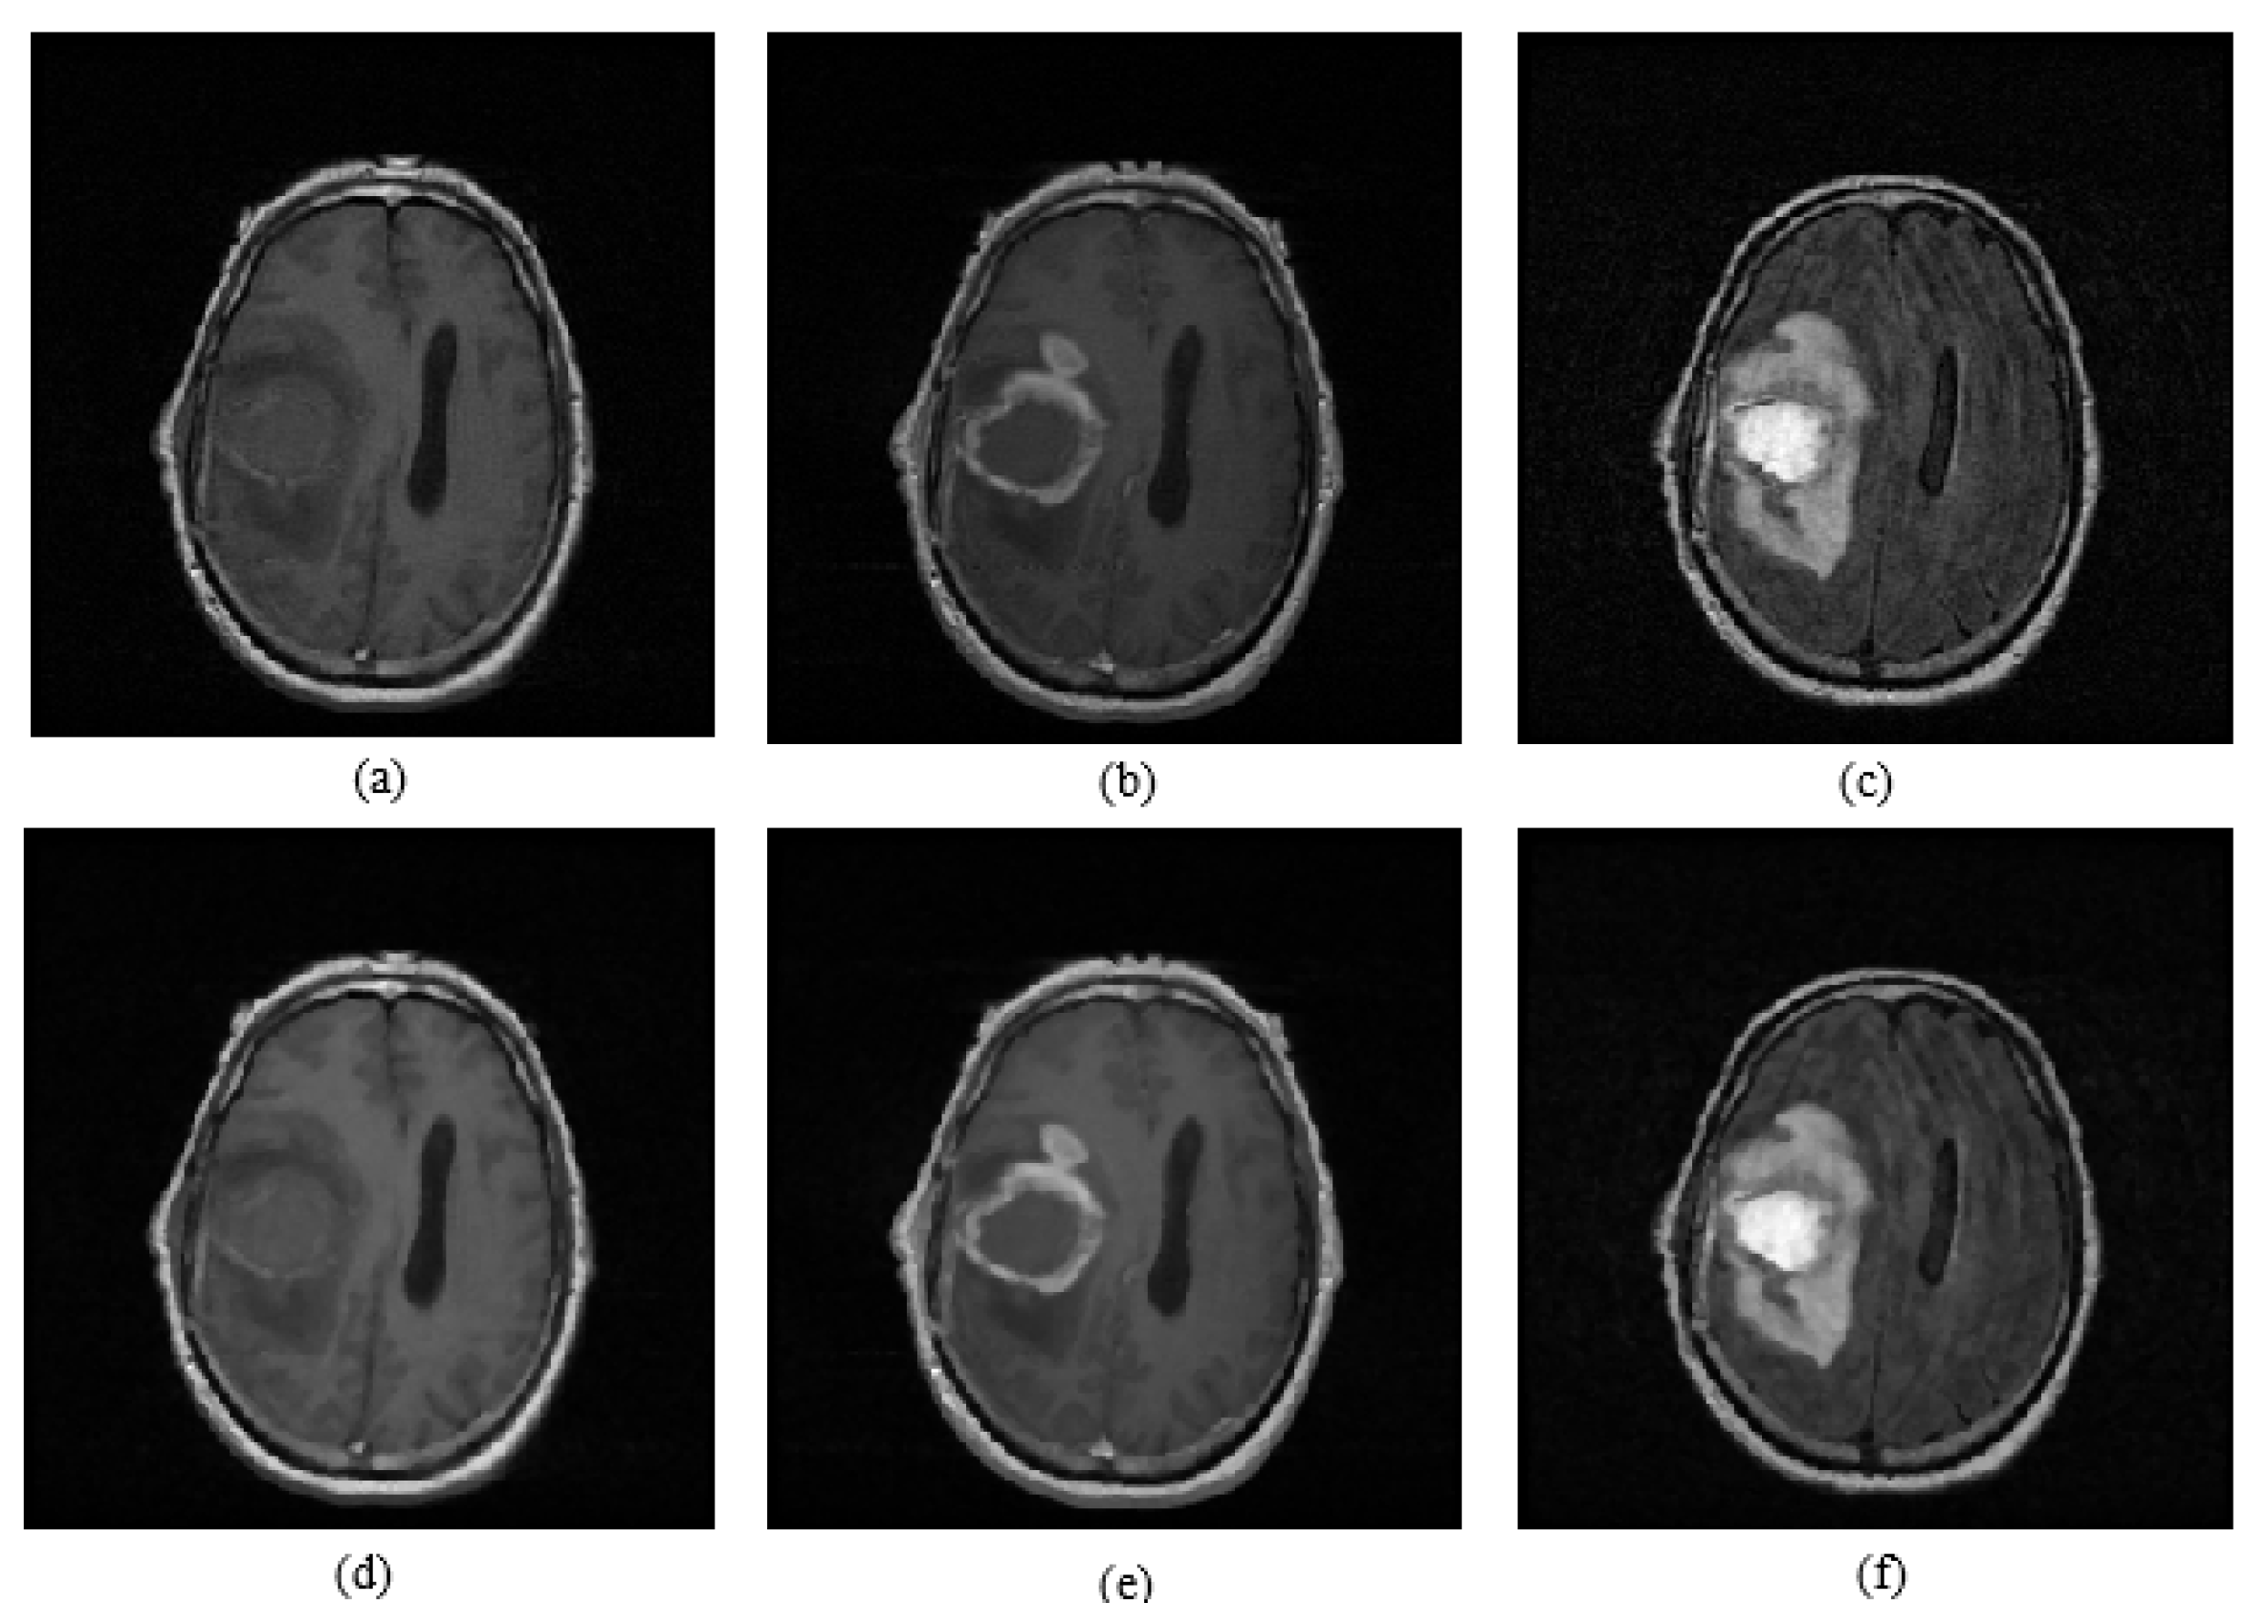

Figure 2.

(a) T1 image; (b) T1C image; (c) FLAIR image; (d) median-filtered T1 image; (e) median-filtered T1C image; (f) median-filtered FLAIR image.